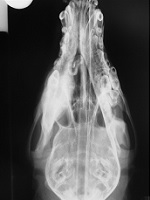

a) On the lateral radiograph a thick brush border perisoteal reaction is visible of the ventral

mandibular cortex. On the dorso-ventral view it appears as if the majority of the reaction is

situated just on one of the mandible and here a radiopaque mass is evident superimposed on the

mandibular 4th premolar and first molar teeth. The radiographic appearance, even being

unilateral, together with the signalment and history makes craniomandibular osteopathy the most

likely diagnosis. Unilateral disease should be differentiated from osteomyelitis, severe

localised periodontitis and neoplasia.